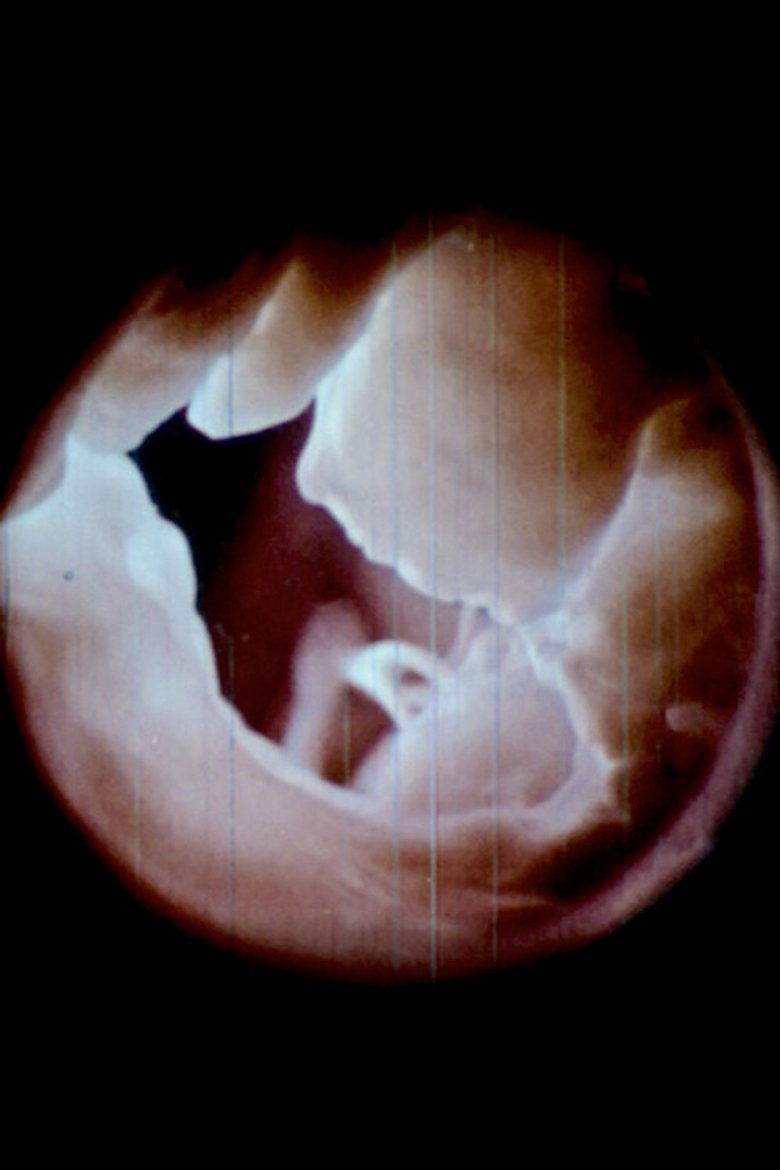

Poster of 心 Heart (Radical 61)

心 Heart (Radical 61)